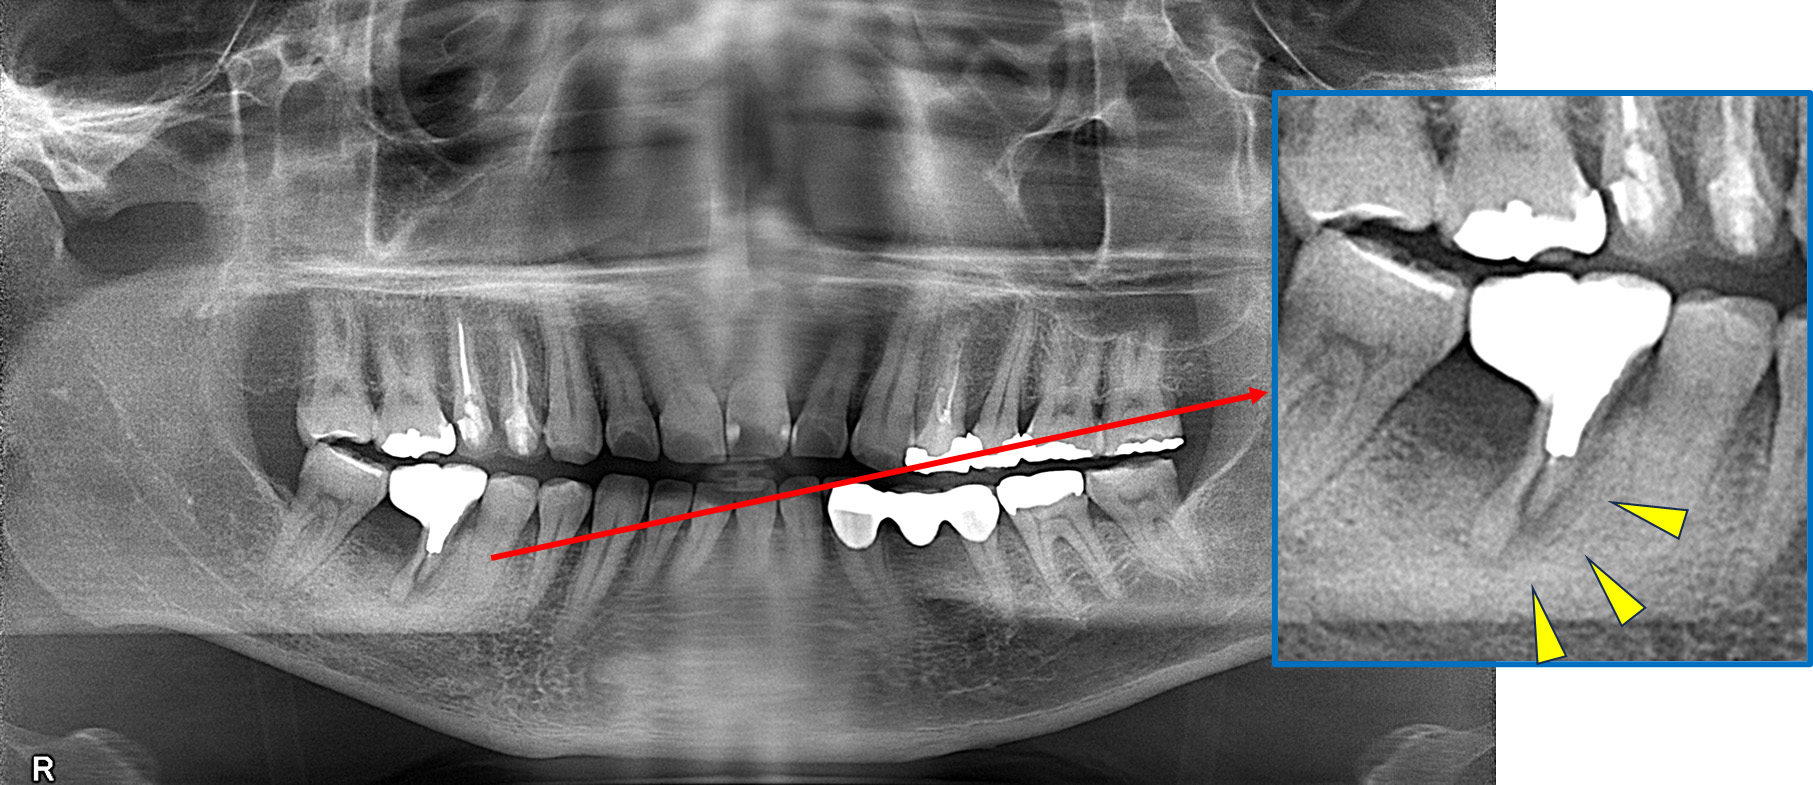

より正確な診断のために(歯科用CT装置)

インプラント治療は診査・診断と治療計画が大切です。

そのためには従来のパノラマ写真に替えて正確に顎の状態を撮影できる3DCTが不可欠です。

当院では、歯科用CTを用いた診査・診断と治療計画を行っています。

パノラマレントゲン写真 -

親抜歯後、歯ぐきは治癒しました。しかし、インプラント治療のためには骨が不足していました。

CT画像 -

骨移植(人工骨+メッシュプレート)を行い、骨を造りました。

インプラント手術を行いました。

レントゲン画像 -

レントゲン画像 治療前 インプラント治療後